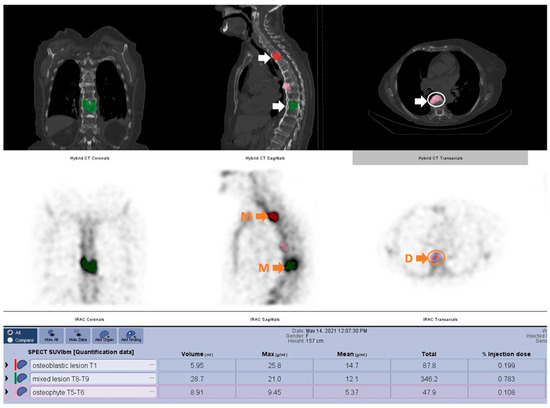

| SUVMax Value | No. | Min. | Max. | Mean | Std.dev. |

|---|---|---|---|---|---|

| Metastatic lesions | 236 | 10.90 | 130.70 | 32.56 | 16.39 |

| Degenerative lesions | 179 | 3.50 | 27.00 | 10.26 | 4.67 |